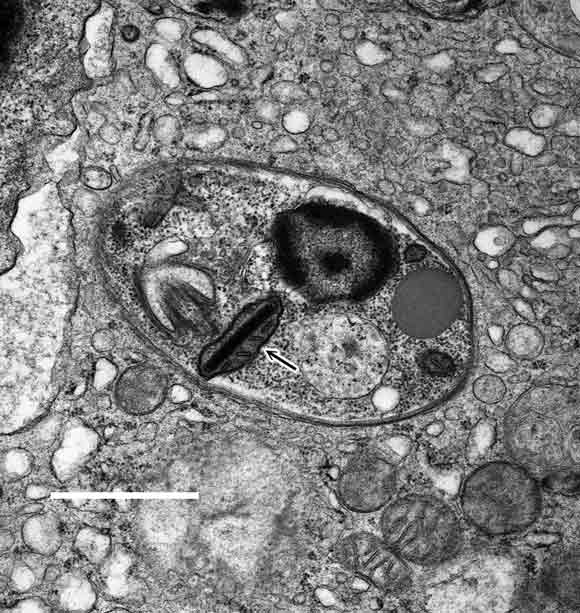

A month after discharge, the pancytopenia persisted. Repeated parvovirus B19 serological testing was negative for both IgM and IgG. A second bone marrow biopsy at this time revealed occasional macrophages containing amastigotes (the resting intracellular stage of leishmaniae, formerly known as Leishman–Donovan bodies; Box 2). Review of the first bone marrow biopsy specimen failed to show any protozoa.

The definitive diagnosis depends on demonstrating either amastigotes in tissue or promastigotes in culture. Splenic puncture is the most sensitive means of obtaining a diagnosis, but biopsy of the bone marrow and liver is almost as good. In immunosuppressed individuals, promastigotes can sometimes be cultured from the buffy layer of centrifuged blood, and amastigotes can be seen in macrophages in biopsy specimens from various tissues. Testing for antileishmanial antibodies is not generally available and may be difficult to interpret.